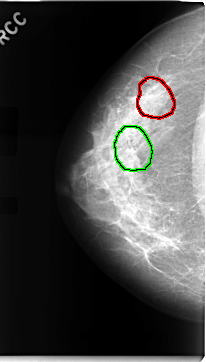

C_0068_1.RIGHT_MLO

FILE: C_0068_1.RIGHT_MLO.OVERLAY

TOTAL_ABNORMALITIES 2

ABNORMALITY 1

LESION_TYPE CALCIFICATION TYPE AMORPHOUS DISTRIBUTION SEGMENTAL

ASSESSMENT 5

SUBTLETY 3

PATHOLOGY MALIGNANT

TOTAL_OUTLINES 1

BOUNDARY

ABNORMALITY 2

LESION_TYPE MASS SHAPE ARCHITECTURAL_DISTORTION MARGINS SPICULATED